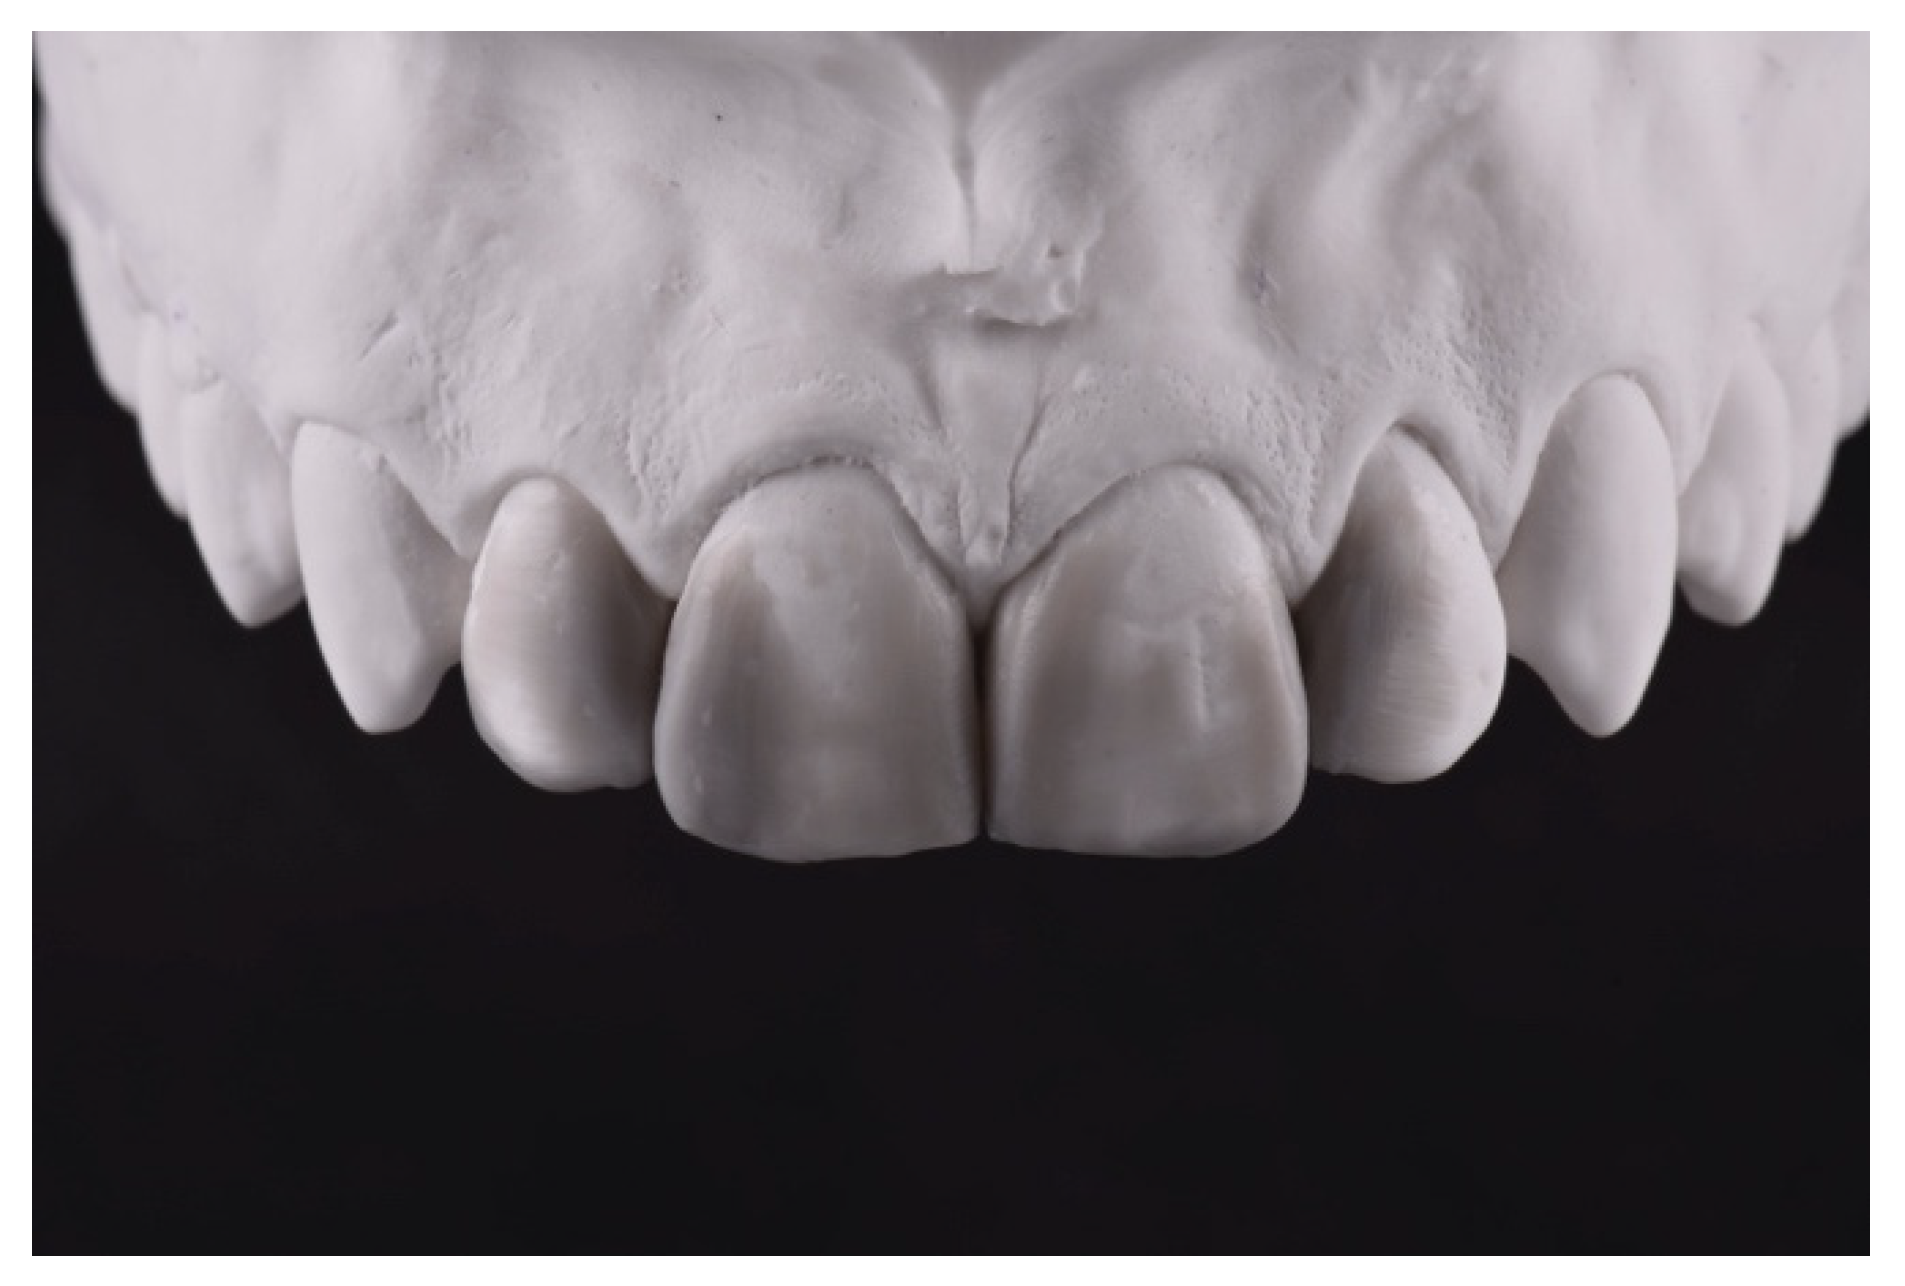

2. Case Presentation